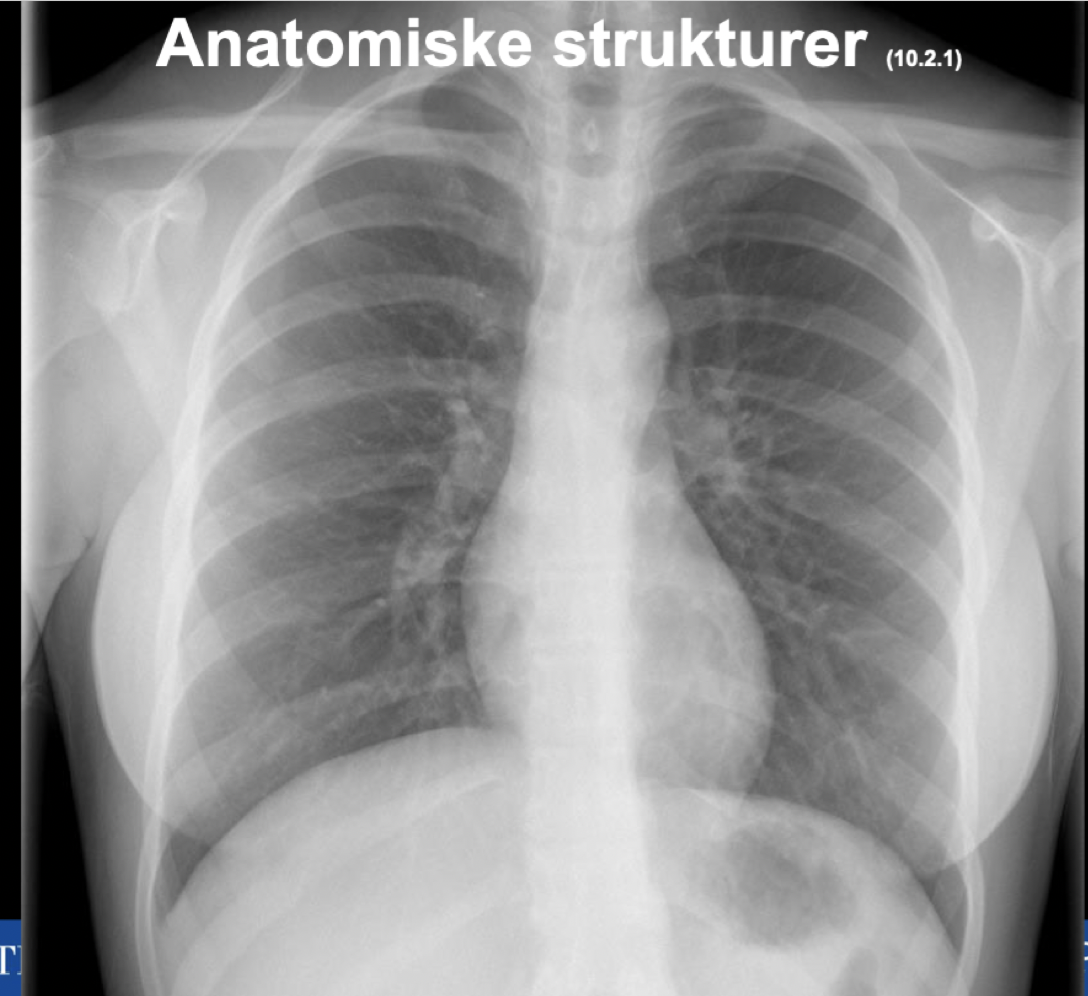

Q

Plasser anatomiske strukturer

A